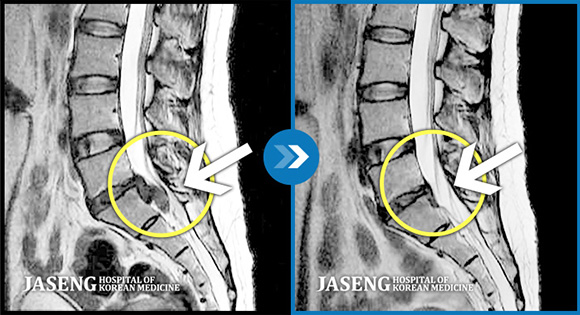

01비수술 치료를 통해 급성 터진 디스크 소멸 가능

터진 디스크 흡수 임상 결과

Complenmentary and

Alternative Medicine, 2017